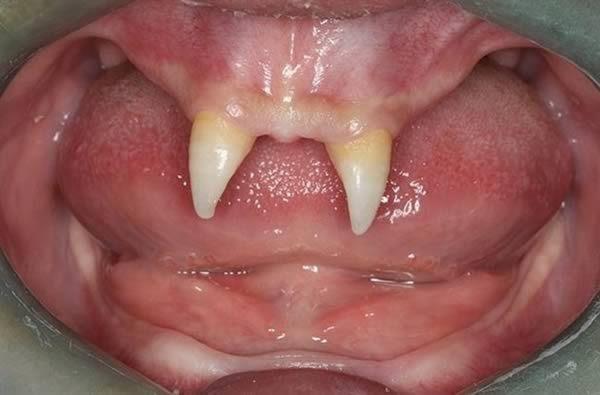

白喉病图片实拍图

白喉病图片实拍图,大人白喉症状图片

咽白喉

白喉病咽部图片

白喉口腔图片